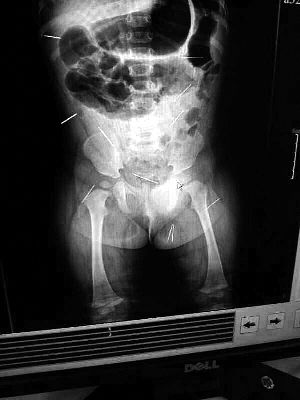

山東聊城11個(gè)月女嬰萱萱(化名)疑似被人以12根鋼針插滿臀部、腹腔等部位,昨天在兒童醫(yī)院會(huì)診后,醫(yī)生稱3根針靠近胸腔最危險(xiǎn),首批先行取出,預(yù)計(jì)將在下周二手術(shù)。孩子父母稱孩子一直由家人照顧,自家與他人并無冤怨。山東警方表示正在偵破中,不便透露案情。

“要不是當(dāng)初那幾個(gè)紅點(diǎn),可能到現(xiàn)在我們還不知道孩子身體里有鋼針!”昨天,在兒童醫(yī)院住院處,萱萱爸爸范先生稱,日前原本很愛笑的萱萱突然變得有些焦躁,一抱起來就哭,孩子母親偶然間在萱萱屁股上發(fā)現(xiàn)了幾個(gè)小紅點(diǎn)兒,原以為是蚊蟲叮咬,就醫(yī)結(jié)果卻讓人不寒而栗?!搬t(yī)院拍出的片子上,萱萱的體內(nèi)有12根鋼針,插滿臀部、腹腔、骨盆等各個(gè)部位?!狈断壬榻B,因?yàn)殇撫樢焉钊塍w內(nèi),要是孩子不哭鬧,他們很難發(fā)現(xiàn)。

北京晨報(bào)記者了解到,目前體內(nèi)的12根鋼針多分布在孩子的臀部,一根在腹部,其余3根在胸腔附近,其中一根很接近心臟?!耙?yàn)楹⒆犹?,醫(yī)生們害怕取針的時(shí)候?qū)λ斐蓚Γ谛厍桓浇?針可能會(huì)威脅她的生命”。